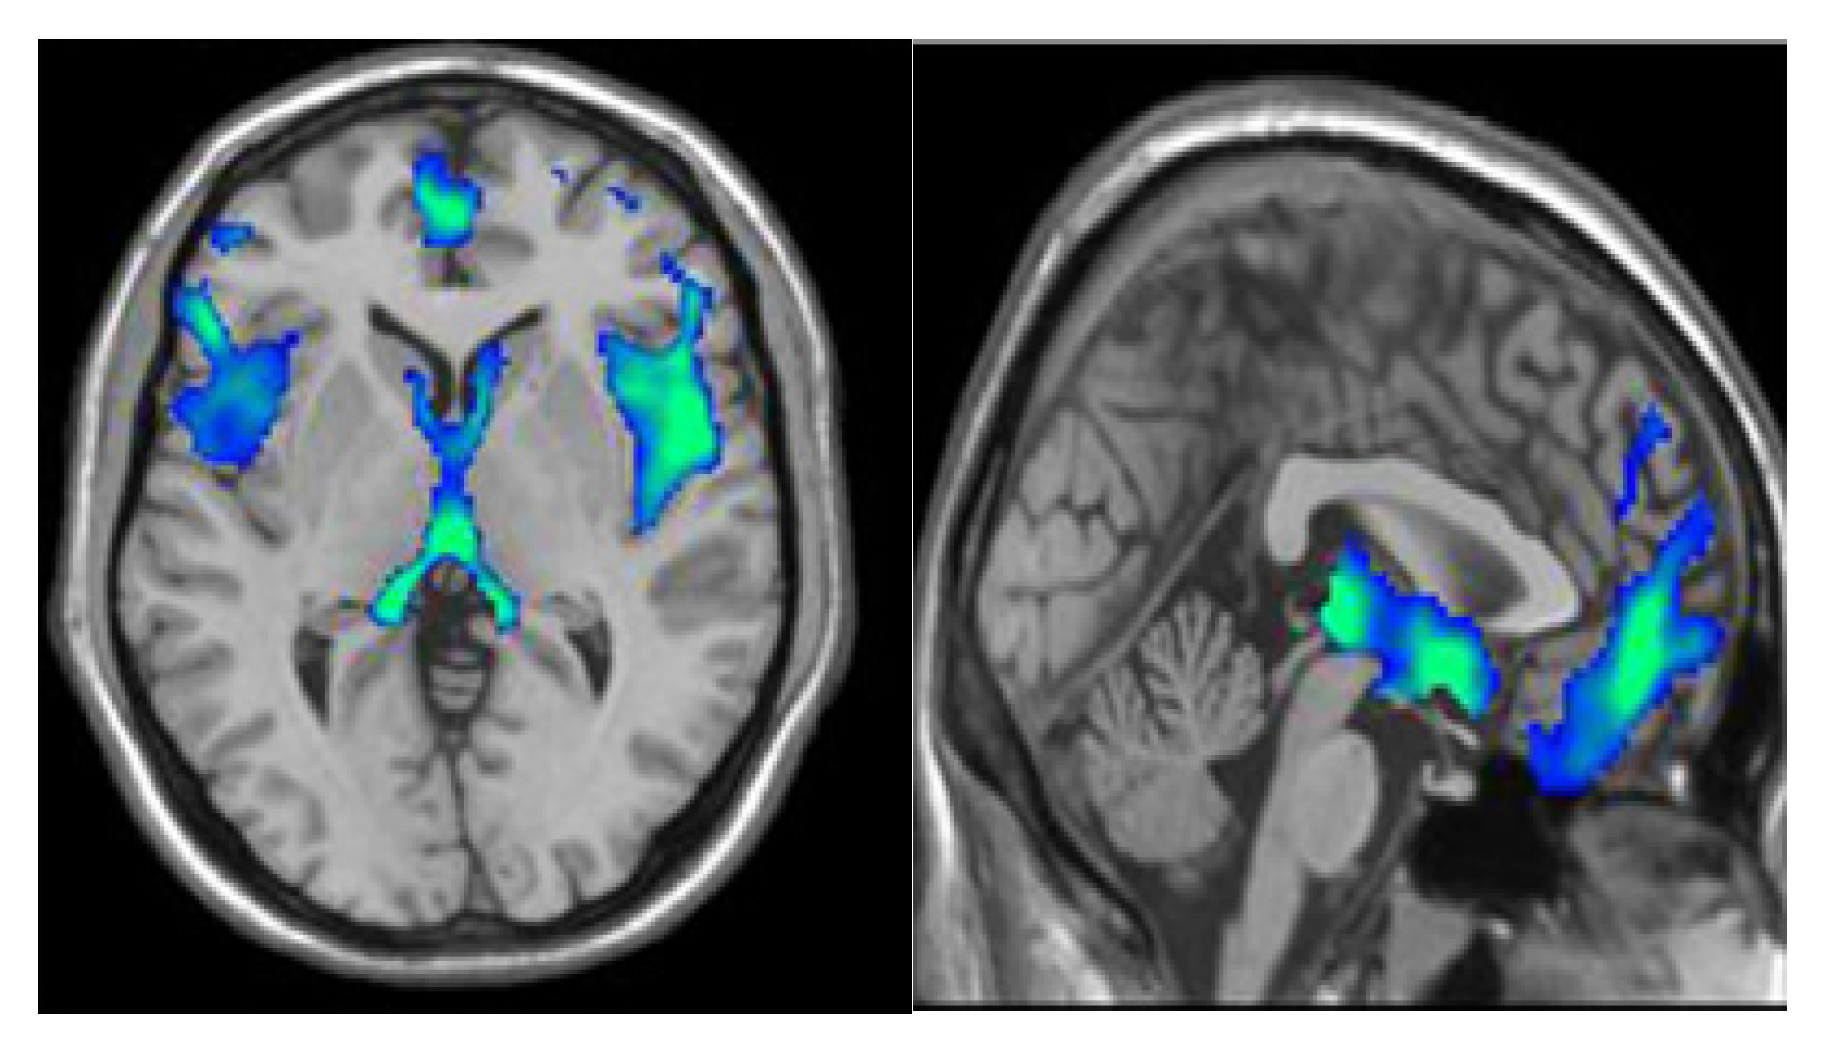

3.1. Database Description and Denoising

3.2. Segmentation